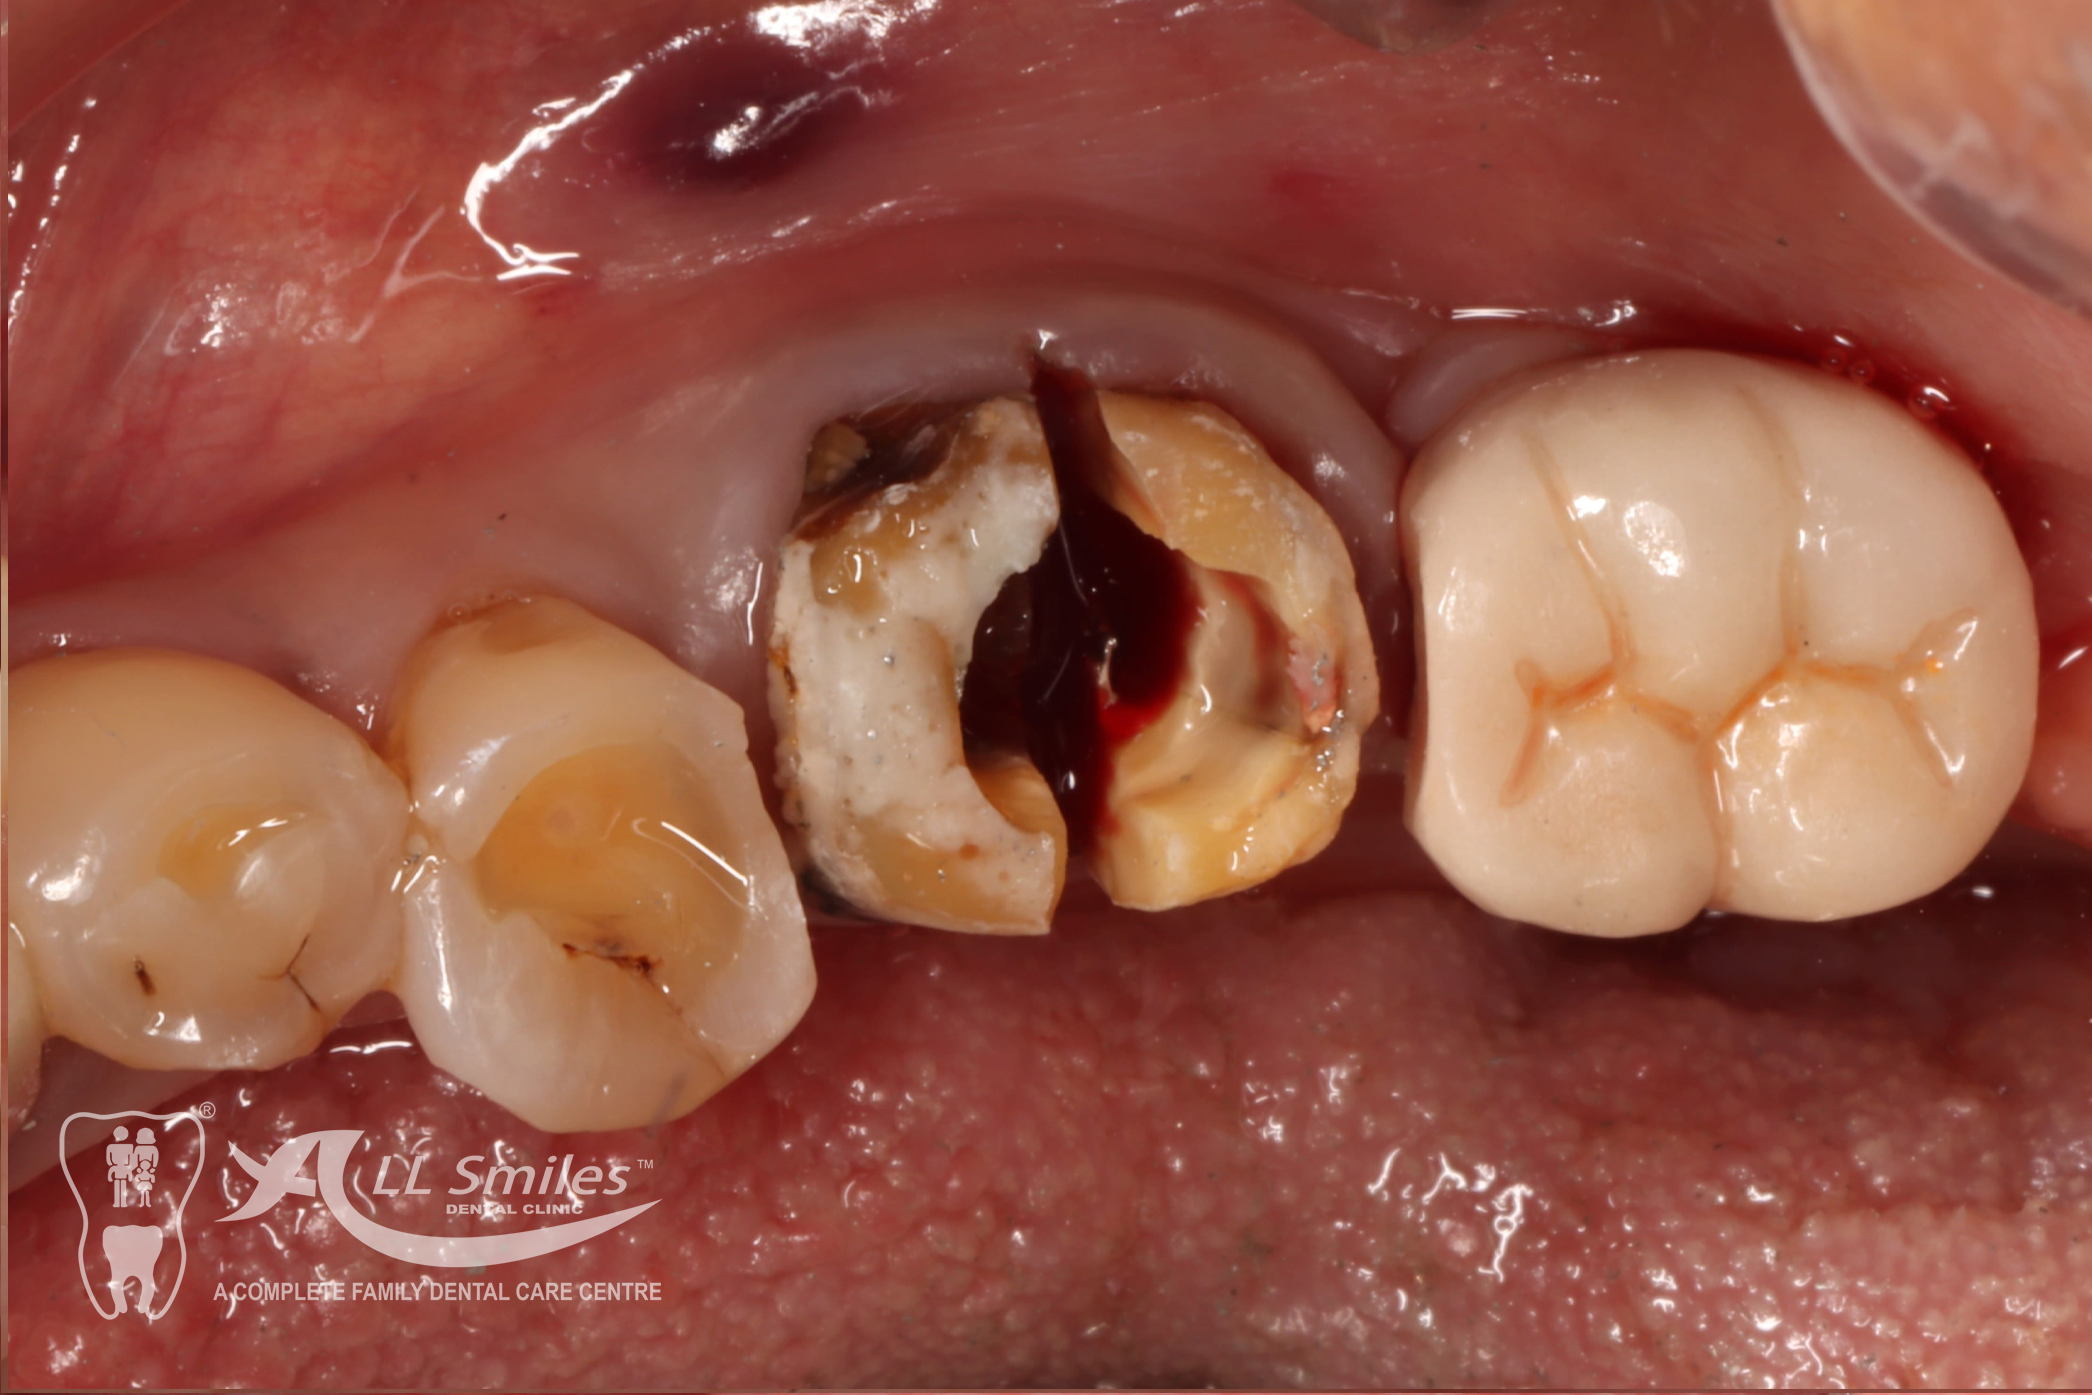

Implants For Multiple Missing or Broken Teeth Regardless of whether one or more teeth are missing in a row: Every tooth is individually replaced and the situation is restored to its original condition. If three or more teeth in a row are missing, you can decide to have an implant- borne bridge. In this solution the new crowns are linked together and depending on the size of the gap are placed on a stable and secure base of two or more implants .

After precise planning the new tooth roots are generally placed in the jaw in one single treatment session. A temporary denture closes the gaps during the healing phase. After healing the final crowns or the bridge are permanently fixed to the implants. Life With Bite! Dental Implants For The Edentulous Jaw.

Dental Implants Gallery